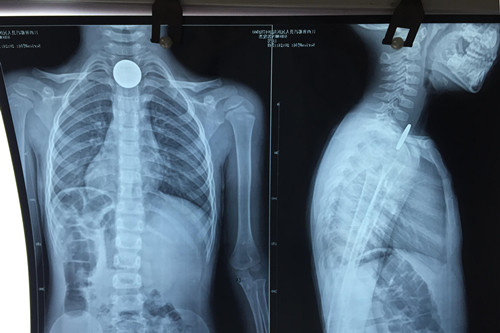

3岁患儿郭某,傍晚时分在家玩耍时口含一枚五角面值的硬币,不慎吞入后反复恶心、呕吐,连喝水都会引发呕吐。就近送至都昌县人民医院行胸片检查,证实硬币嵌顿于食道入口处,建议转上级医院就诊。晚上22:00左右赶到九江市,在专科医院挂急诊就诊,因无对口科室急诊,在其总值班医师的指引下,来到临床医学院/附属医院耳鼻喉科就治。当班医生游锦接诊后,成功取出硬币,稍作观察,患儿于23:30左右离院回家。

对于如何取出硬币,游医生介绍说,小儿食管异物取出比较棘手,例如这位3岁患儿,来院就治时已距误吐硬币达6小时左右,异物刺激强烈,难受哭闹,很难配合治疗。以往这种情况多采用全麻下硬质食管镜取食管异物,患者甚至需住院两至三天。从今年5月以来,临床医学院/附属医院开始利用导尿管来取小儿食管异物这一新方法,现已成功治疗了数十名误吞异物的小朋友。因为导尿管柔软细小,引起咽反射轻微,不会引起患儿的较大恐惧感, 在表麻或者局麻下即能配合,手术安全高效。大部分情况下也不需住院,花费明显减少。